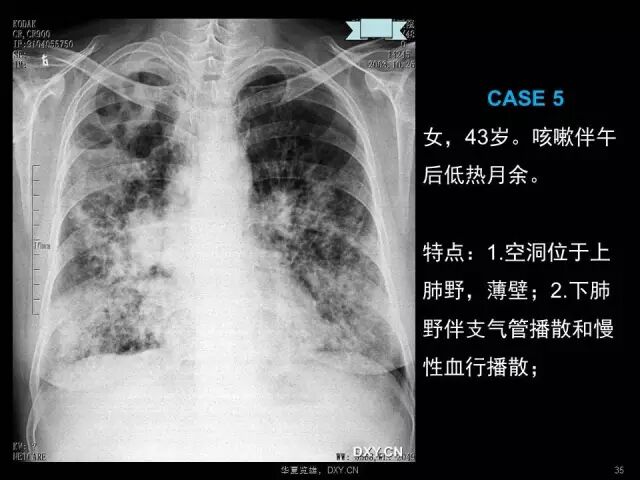

肺炎、肺癌、肺结核在影像学上的征象往往千变万化。